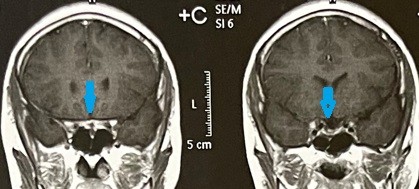

tumor of the base of the skull pressing on the right optic nerve